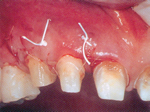

| 骨が無くなってしまっています | 再生を促す薬です | 薬を塗布した後すぐ縫合 |